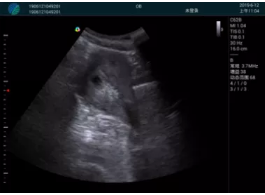

急診醫(yī)學(xué)的核心任務(wù)是對危重急的病人進行快速診斷并進行生命支持,在病人處理中的時效性和整體性顯得尤為重要。時效性是指要迅速及時的對病人的狀況作出初步診斷,同時采取相應(yīng)的有效措施,以挽救病人的生命。高效率的緊急救援,是政府機關(guān)、醫(yī)院對外形象展示的重要窗口,是衡量一個地區(qū)醫(yī)療技術(shù)及管理水平的重要標志。為了適應(yīng)新時代急救系統(tǒng)的發(fā)展,新設(shè)備新技術(shù)在急救系統(tǒng)的應(yīng)用顯得越來越急迫??颠_i-M20便攜平板彩色超聲作為一種快速、無創(chuàng)的檢測設(shè)備在急救系統(tǒng)的應(yīng)用越來越普遍。

M20便攜超聲在臨床中的應(yīng)用:

超聲引導(dǎo)下可視化人流是技術(shù)安全性的保障,一般對人流術(shù)設(shè)備預(yù)算不高,M20具備婦產(chǎn)科軟件包,且穿透力圖像質(zhì)量好,既滿足人流引導(dǎo)需要,也可用于床旁超聲的需求。

高精尖的超聲技術(shù)、簡約小巧的平板全觸控設(shè)計、領(lǐng)先的移動信息平臺、優(yōu)異的臨床探頭使得M20成為當(dāng)今世界便攜式超聲設(shè)備家族中的佼佼者。M20采用高通CPU,Android 操作系統(tǒng);固態(tài)硬盤超大內(nèi)存及海量數(shù)據(jù)存儲,極大地提高了臨床超聲檢查效率,加速了工作流程。